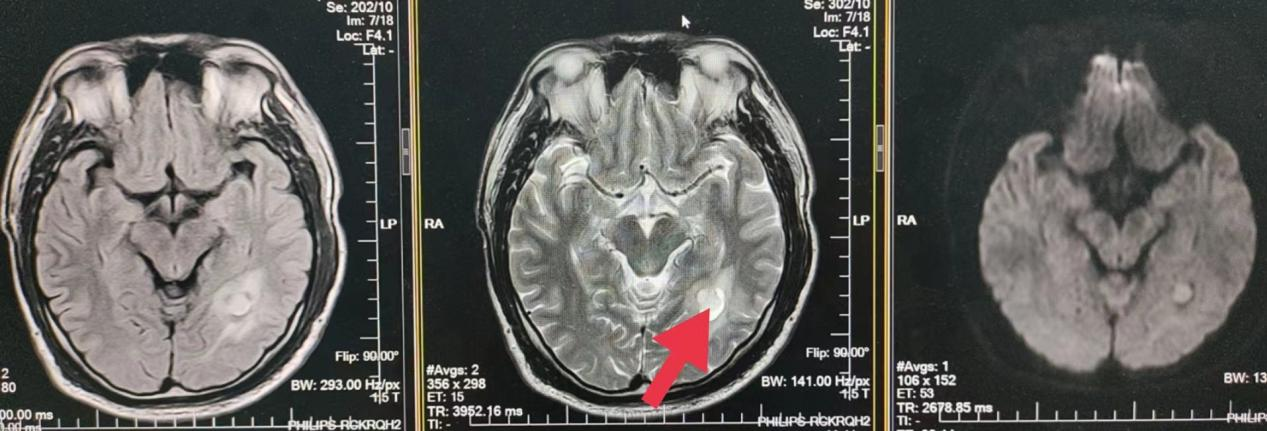

07、**男士,58岁

于2023年8月18日在邯郸仁泰北区体检,脑核磁检查提示:左侧枕叶可见囊实性混杂信号,大小约1.8cmX1.3cm,周围可见片状水肿影。诊断: 左侧枕叶异常信号,建议客户到三甲医院进一步检查。2023年8月29日跟踪回访,客户告知,神经外科诊断脑肿瘤,已住院准备手术。